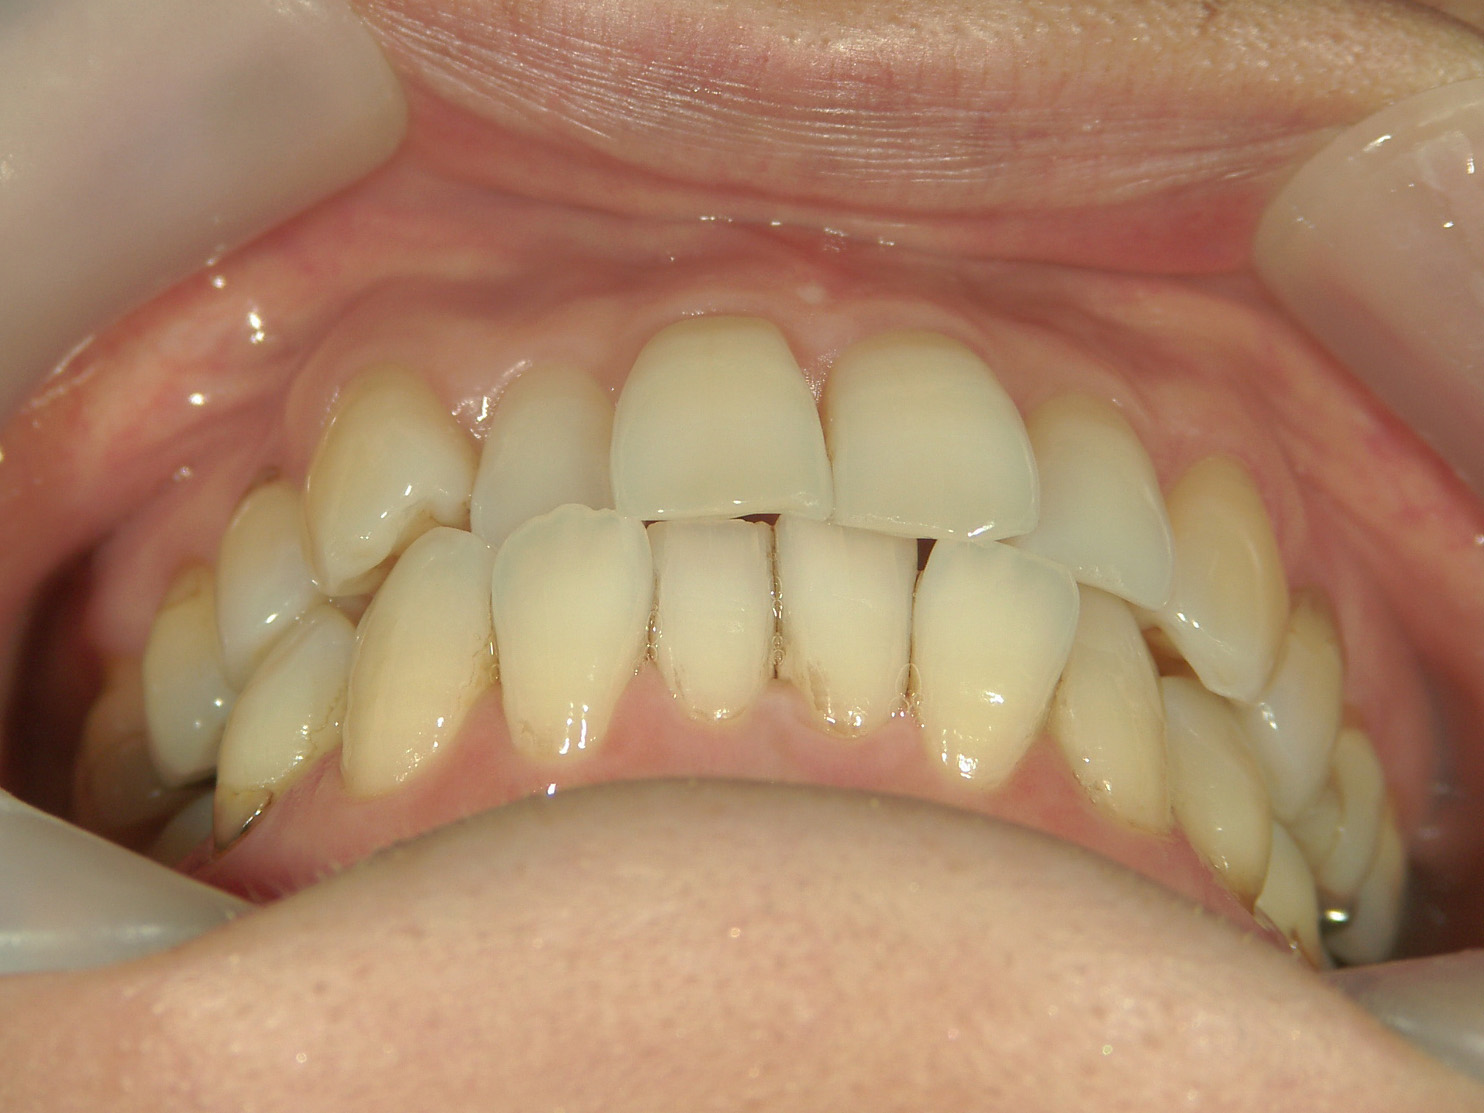

インビザライン矯正 症例(25)

主訴: ㊤前歯が出ていて、噛み合わせが気になる。

カテゴリー : ガタガタ(叢生)